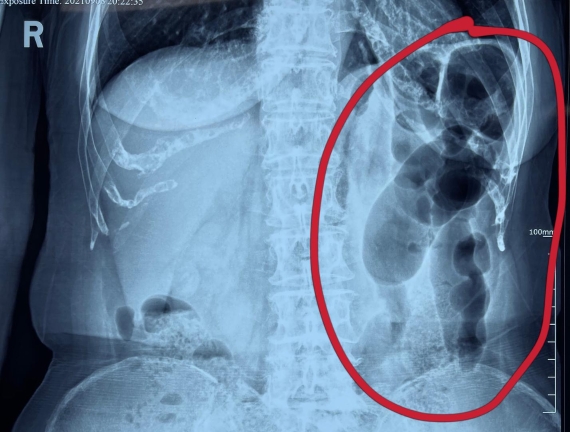

據(jù)省醫(yī)院消化病院消化二科姜子曄醫(yī)生介紹,韓大娘今年已經(jīng)73歲,家住哈爾濱市,一周前開始腹脹腹痛,有較為明顯的左側(cè)腹部疼痛,疼痛劇烈時(shí)會出現(xiàn)左側(cè)腹部鼓包情況,排氣排便后有所好轉(zhuǎn)。韓大娘家人見狀將其送到了黑龍江省醫(yī)院,門診檢查腹部平片提示為左側(cè)腹部積氣,口服全消化動力藥及通便治療后腹痛腹脹有所緩解,入院前再次突發(fā)左側(cè)腹痛加重伴有明顯腹脹,急診隨后以“腹痛腹脹原因待查”將韓大娘收入到消化病院消化二科。

姜子曄醫(yī)生熱情接待了韓大娘,為其進(jìn)行了仔細(xì)查體,除了左側(cè)腹部壓痛并未見明顯異常,對癥給予灌腸后,韓大娘的腹脹有所緩解,第二天姜子曄醫(yī)生為韓女士進(jìn)行了胃腸鏡檢查,也未見明顯異常。但此時(shí)韓大娘腹部平片結(jié)腸腸管擴(kuò)張仍然很嚴(yán)重,腹痛腹痛也沒緩解,到底什么原因呢?消化二科主任陸以霞在查房時(shí)建議繼續(xù)給予韓大娘口服全消化動力藥,必要時(shí)灌腸治療,同時(shí)陸以霞主任在追問病史查體時(shí)發(fā)現(xiàn)韓大娘左下腹紅色皮疹和小水泡,反復(fù)抓撓腹部皮膚部分已結(jié)痂,高度懷疑為帶狀皰疹。